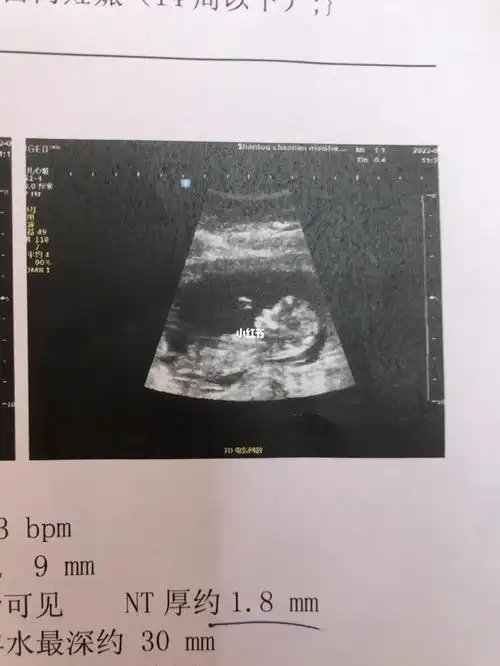

nt一次过帮我看看是小男生还是小女生呀